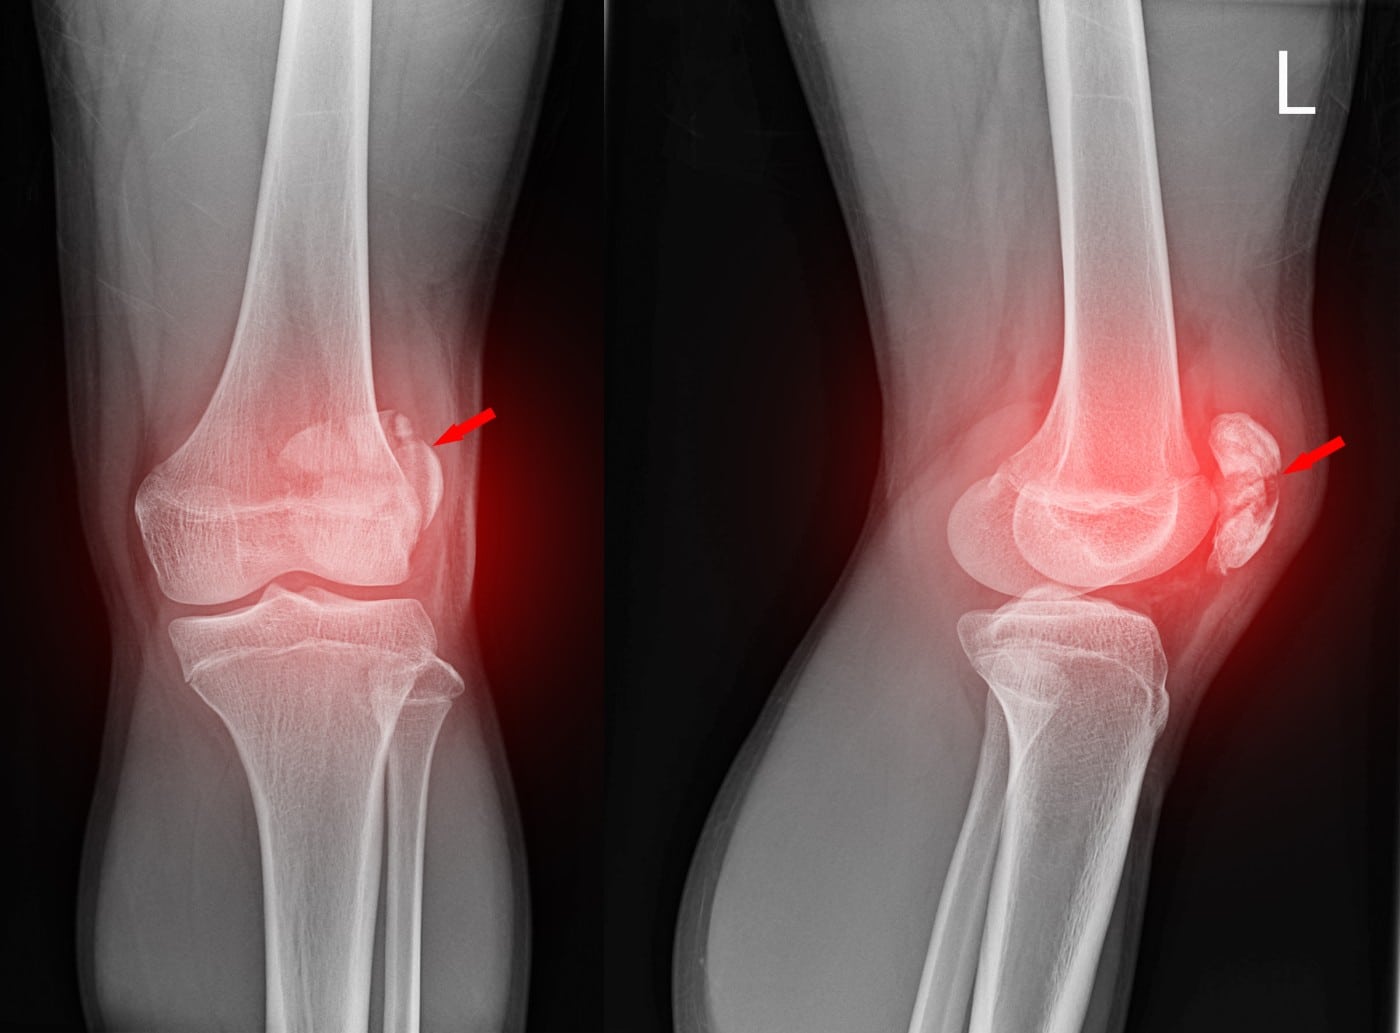

Complex Knee Fractures (Trauma)

A complex fracture, simply put, is a fracture that is more severe in nature. It usually involves injury to multiple joints and their associated tendons and ligaments. It is not uncommon for complex fractures to cause the fractured bone to pierce the skin into the external environment.

These fractures are often a result of high-velocity impact such as vehicular accidents, falls from high heights.

Extreme pain is present with most complex fractures. Severe disability and inability to move the relevant bones and joints are also natural sequelae. Visibly protruding bones are also common, and may even break the skin barrier from within.